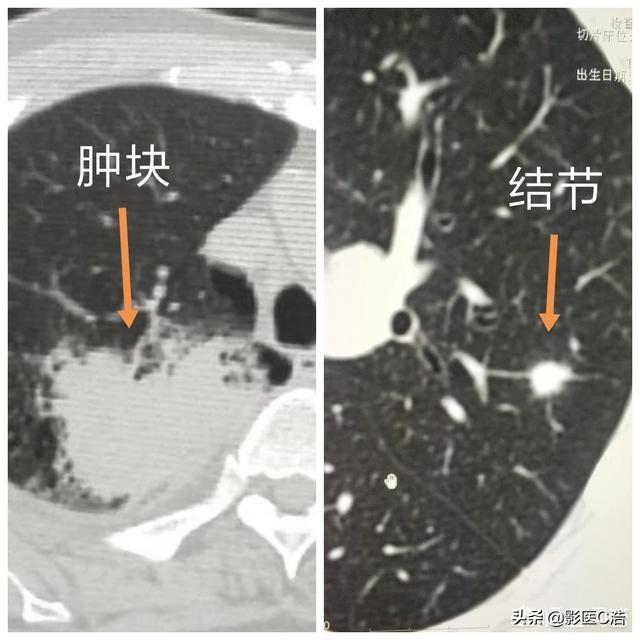

Knötchen werden in feste und gemahlene Glasknötchen unterteilt

Lungenknoten werden je nach ihrer Dichte in verschiedene Typen eingeteilt: Knoten mit höherer Dichte, die auf dem CT der Brust als weiße Punkte erscheinen, werden als solide Knoten bezeichnet, während Schliffknoten eine geringere Dichte haben und wie Wasserdampf auf dem Glas aussehen. Glasschliffknötchen, insbesondere reine Glasschliffknötchen, sind in der Regel bösartiger.

In der chinesischen medizinischen Leitlinie heißt es zur Definition des Lungenknotens: Die Bildgebung (Thorax-CT) zeigt einen fokalen, rundlichen, festen oder subsoliden Lungenschatten mit einer erhöhten Dichte und einem Durchmesser von ≤3 cm, der isoliert oder mehrfach vorhanden sein kann und nicht von einer pulmonalen Atelektase, einer Vergrößerung der hilären Lymphknoten und einem Pleuraerguss begleitet ist.

Im Allgemeinen wird jeder Schatten mit erhöhter Dichte in der Lunge mit einem Durchmesser von weniger als 3 cm als Lungenknoten bezeichnet, und der Grad des Risikos hängt nicht nur von der Größe ab, sondern muss auch in Verbindung mit der Morphologie, der Dichte und der Geschwindigkeit der Vermehrung des Knotens bestimmt werden.

Zunächst einmal ist es wichtig, die Definition von Lungenknötchen zu verstehen. Nach dem jüngsten chinesischen Expertenkonsens über die Diagnose und Behandlung von Lungenknoten ist ein Lungenknoten definiert als ein fokaler, abgerundeter, hyperdichter, fester oder subfester (gemahlener) Lungenschatten von ≤ 3 cm in der Lunge, der nicht mit pulmonaler Atelektase, Lymphknotenvergrößerung oder Pleuraerguss einhergeht. Die Lungenknötchen können isoliert oder multipel sein. Ist die Läsion größer als 3 cm, spricht man nicht von einem Knoten, sondern von einer Masse, und bei den meisten Massen handelt es sich um Lungenkrebs. Außerdem hängt die Stadieneinteilung bei Lungenkrebs auch von der Größe ab: Je größer der Tumor ist, desto später erfolgt die Stadieneinteilung, was auch bedeutet, dass die Wahrscheinlichkeit einer Bösartigkeit umso größer ist, je größer der Knoten ist.